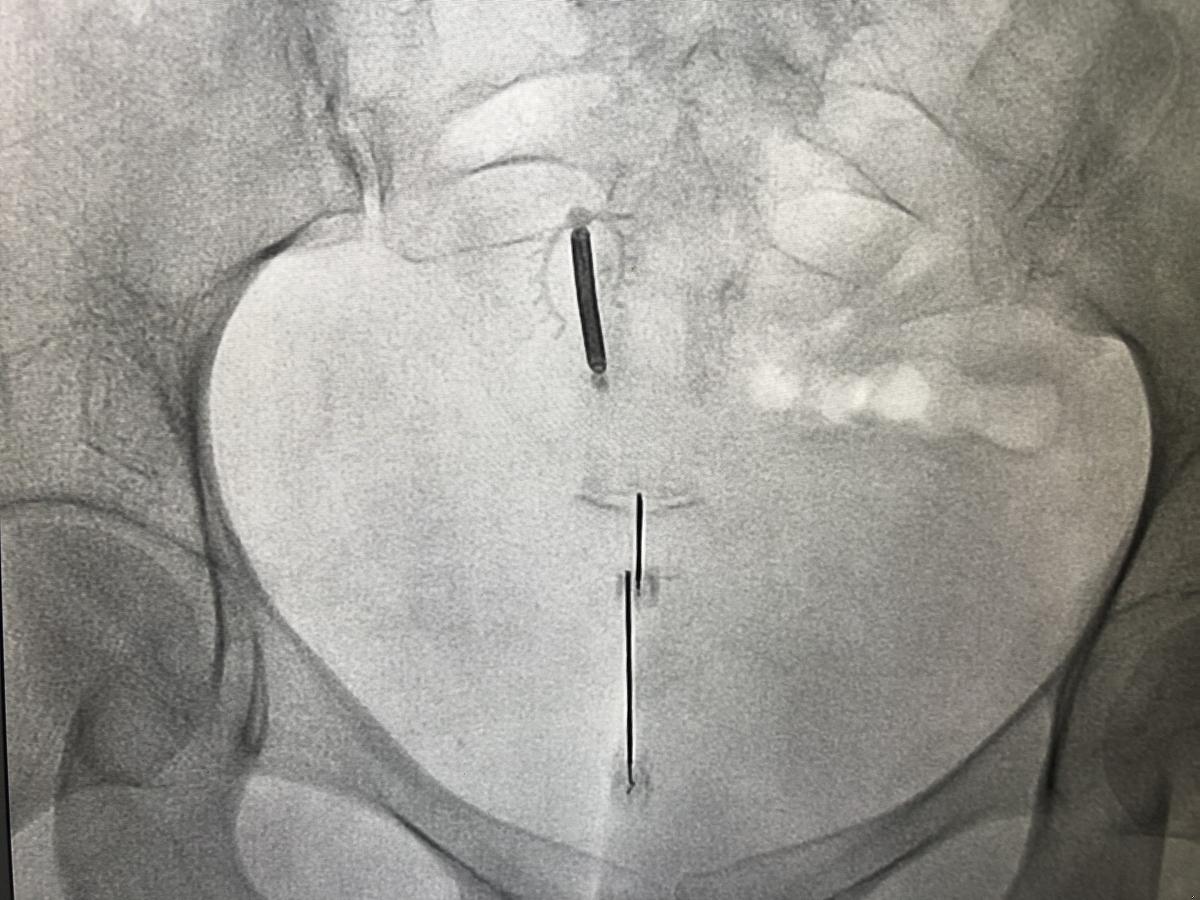

Doctor performing a coccyx injection procedure under image guidance